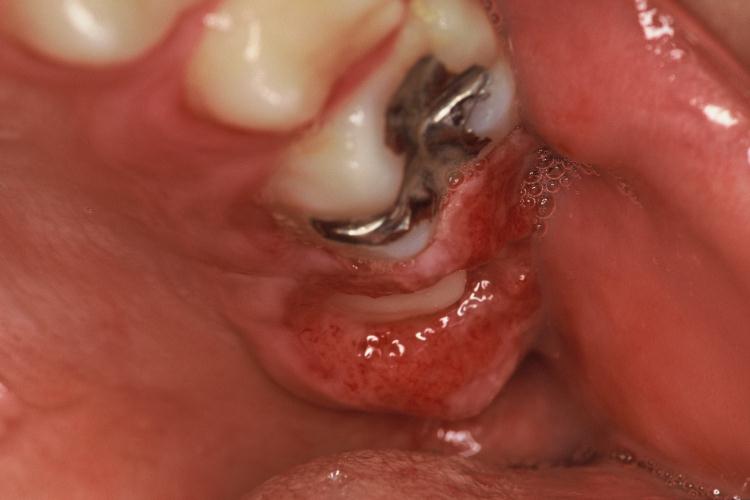

「親知らず」を抜こうと歯医者さんに行っても「口腔外科で抜いてください」と言われる場合があります。

また、親知らずの生え方によっては、困難な手術になってしまう場合があり、口腔外科を勧められることがあります。

ご安心ください。そうぜん歯科クリニックでは、一般的に病院の口腔外科で処置するような「親知らず」でも、歯科大学の口腔外科にで経験を積んだ院長が的確に対応します。

簡易的なCTスキャンではなく、病院歯科にあるような本格的なCTスキャンを使った立体的な画像を基にした「診査・診断」と、高い口腔外科技術により、安心して「親知らず」の抜歯に対処しています。